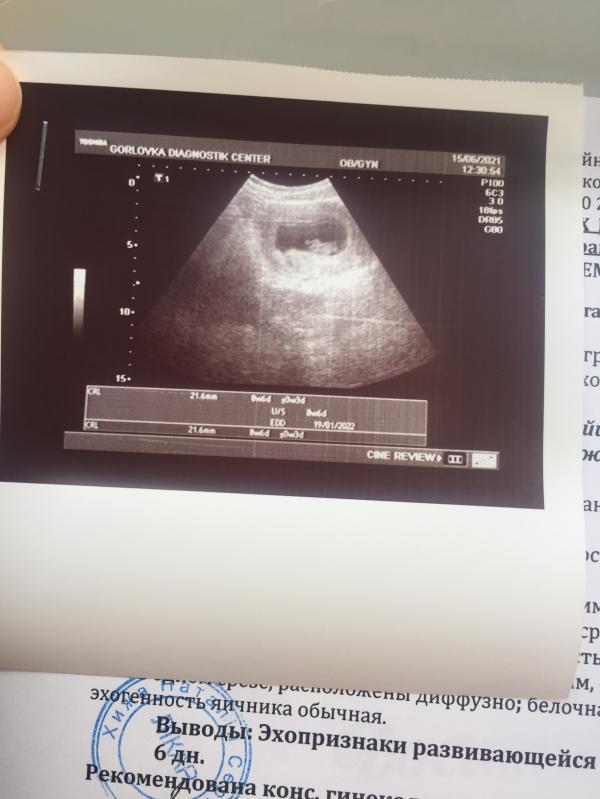

Сегодня была на УЗИ) Всё хорошо) Кроха растет и развивается) Уже даже сердечко видно и слышно❤️ До этого УЗИ еще была в подвешенном состоянии, не могла осознать, что беременна и что всё хорошо, но теперь я спокойна😌